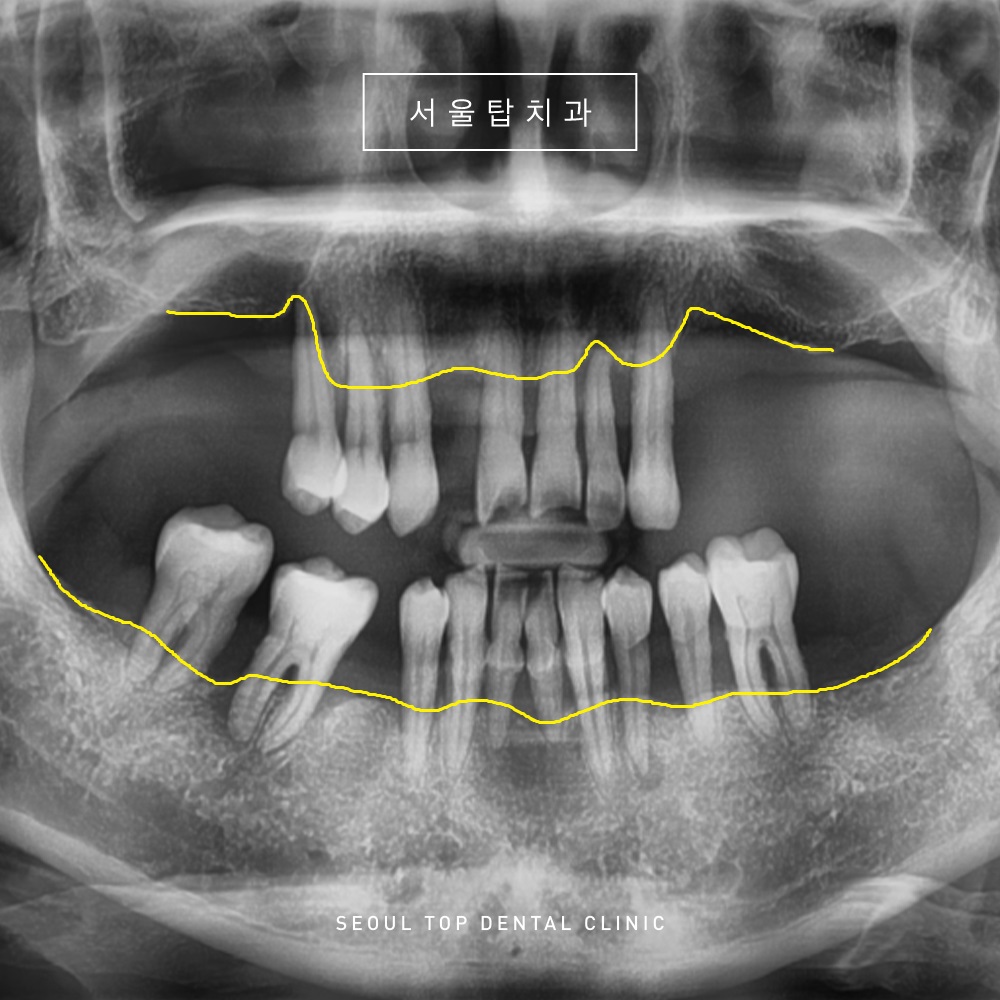

위의 환자분께서는

저작에 불편함을 느껴

치과에 내원을 해주셨는데요.

전반적으로 치아 상실과 더불어

잇몸뼈도 많이 녹아 남아있는 치아들도

많이 흔들리는 상태였습니다.

노란색 표시의 선을 보시면

잇몸뼈가 치아 뿌리에만 걸쳐져 있어

뿌리만 대롱대롱 달려 있는 상황입니다.

물론 가능하다면 치아들을

살려 사용할 수 있으면 좋겠지만,

해당 치아들은 도저히 살릴 수 없는 상황이었습니다.